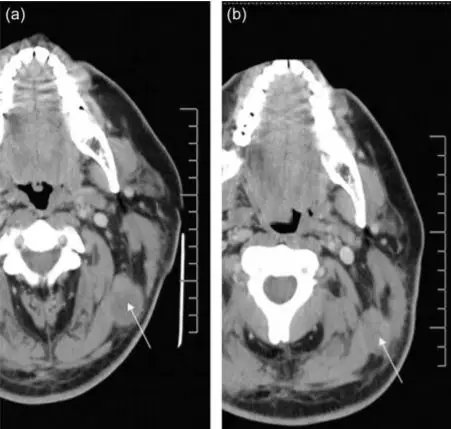

2008年,美国拉什大学医学中心的研究人员将外源扩增的NK异体细胞注入到黑色素瘤患者体内,结果发现,注入注入NK细胞后,该患者左上颈部肿瘤的体积明显降低(从3.15 cm×2.54 cm减小至2.46 cm× 1.76 cm)。同时,该研究也为外源扩增的NK异体细胞是否可以大规模应用于治疗黑色素瘤提供了一定的理论依据。

△ NK细胞治疗前后对比图